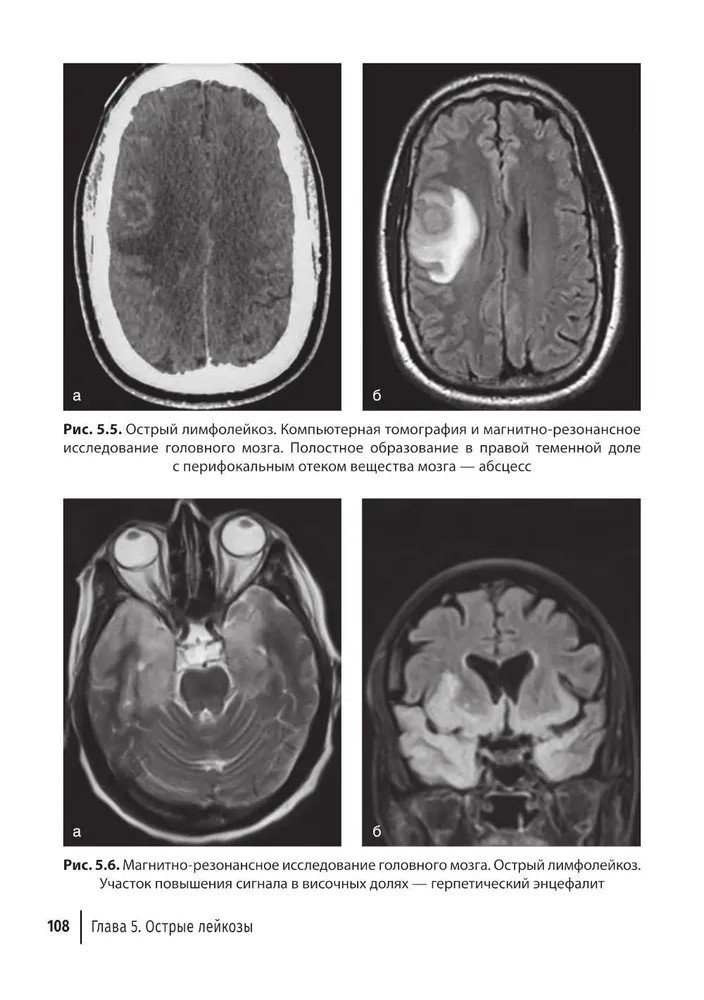

💳 Оплатить за товар можно при получении 🇰🇿 Есть бесплатная доставка по Казахстану 🎁 Копите бонусы с каждой покупки В руководстве представлен широкий спектр сведений, касающихся лучевой диагностики заболеваний системы крови. Охарактеризованы патологические изменения органов и тканей, выявляемые всеми доступными методами лучевой диагностики. Это классическое рентгеновское исследование, ультразвуковое исследование, компьютерная томография, магнитно-резонансная томография и позитронно-эмиссионная томография. Наиболее подробно освещены заболевания, относящиеся к гемобластозам (лейкемии, лимфомы, множественная миелома), также уделено внимание незлокачественным болезням (анемии). Издание содержит большое количество иллюстраций. Информация четко структурирована, что делает удобным использование руководства в качестве справочного пособия. При создании руководства основной акцент был сделан на его полезности в повседневной практической работе. Издание адресовано врачам-гематологам, рентгенологам, онкологам и врачам других специальностей, а также может быть использовано при обучении студентов, аспирантов, ординаторов и слушателей сертификационных курсов и курсов повышения квалификации. |